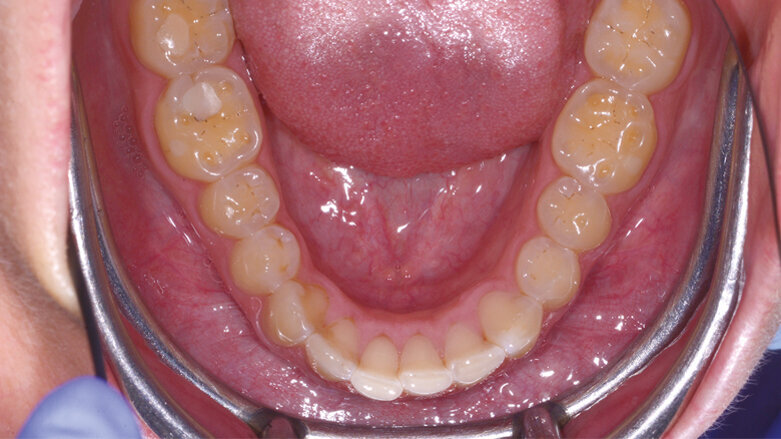

Nel seguente caso clinico, viene eseguita una riabilitazione ultraconservativa da canino a secondo molare su un giovane paziente che denuncia una perdita di dimensione verticale a causa di erosioni e abrasioni che interessano tutti gli elementi del mascellare inferiore da canino a secondo molare.

Fig. 1a_Caso iniziale: il paziente presenta perdita di dimensione verticale a causa di erosioni e abrasioni.

Fig. 10_Caso finale dopo aver eseguito i restauri ultraconservativi.